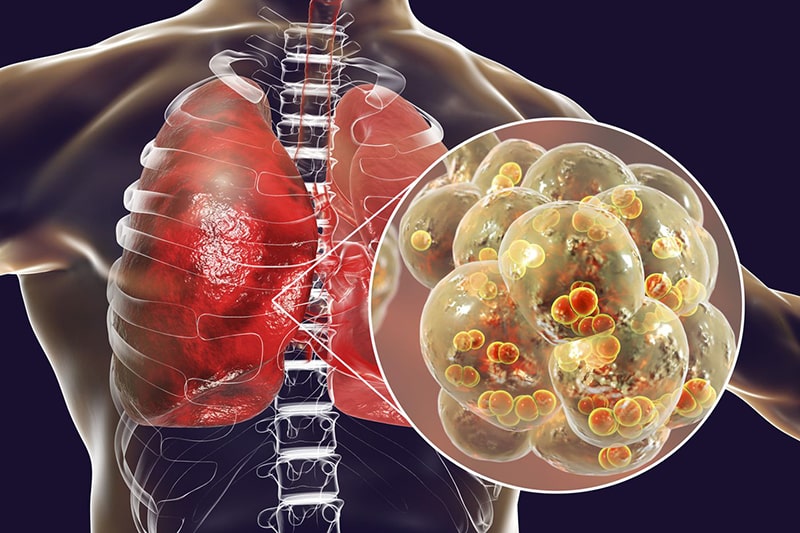

Viêm phế quản là tình trạng niêm mạc ống phế quản- bộ phận có vai trò giữ lại những hạt bụi, chất độc hại và đưa chúng ra ngoài cơ thể, giữ sạch đường thở- bị viêm nhiễm dẫn đến các vấn đề về thanh quản, họng, viêm mũi v.v. khiến cho bệnh nhân gặp khó khăn trong việc hít lượng khí Oxi cần thiết, trong khi lượng khí CO2 độc hại vẫn tích tụ lại. Hãy cùng Doctor có sẵn tìm hiểu rõ hơn về bệnh lý này trong nội dung dưới đây.

Viêm phế quản phổi nếu không điều trị kịp thời và dứt điểm sẽ gây ảnh hưởng xấu đến hệ miễn dịch của người bệnh, có thể gây nguy hại đến chức năng của các bộ phận khác trong cơ thể.

Tiến triển thành bệnh viêm phổi

Tình trạng nhiễm trùng ở phổi, các mô xung quanh phổi sưng tấy và có thể có mủ được gọi là bệnh Áp xe phổi. Bệnh thường gây sốt cao, ho ộc ra nhiều mủ đặc quánh, cơ thể yếu ớt và chán ăn v.v. bệnh có thể lây lan qua đường không khí, đường máu và có nguy cơ gây tử vong cao.